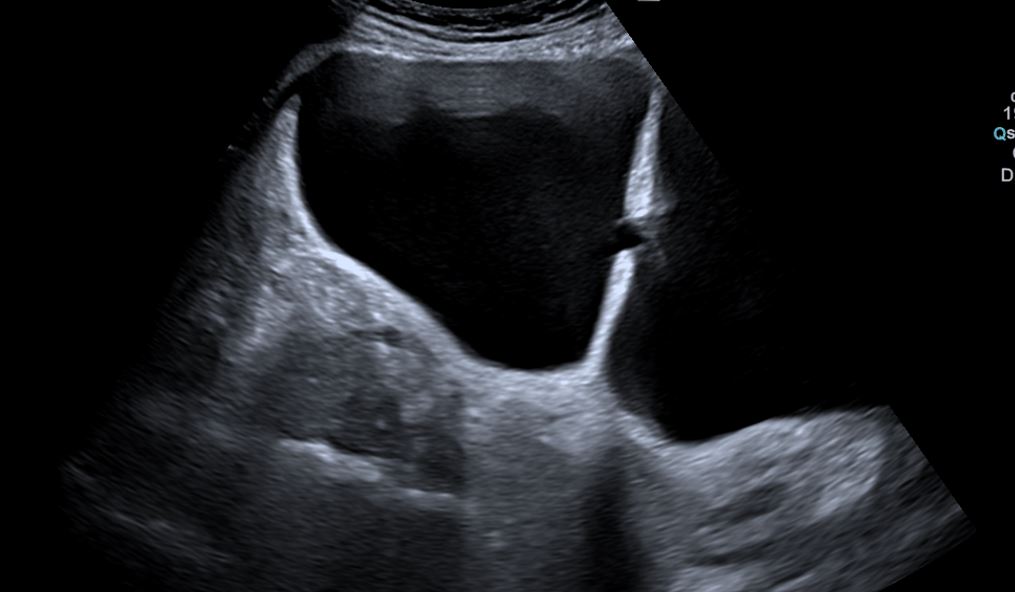

Riñones de tamaño y morfología normales. No observamos litiasis ni dilatación de la vía urinaria. A nivel de la vejiga presenta un tabique con comunicación a una gran cavidad en la pared lateral derecha que da la impresión de que existen dos vejigas urinarias. No hay lesiones parietales. Próstata 32 cc. Volumen premiccional de la cavidad mayor 350 cc y posmiccional 210 cc.

Gran divertículo de vejiga urinaria.

Vejiga urinaria con presencia de jets ureterales, de paredes lisas con un gran divertículo en la pared lateral derecha de 543 cc premiccional que vacía a la mitad en posmiccional 310cc (57%).Volumen vesical premiccional 620cc y posmiccional 179 cc (28%).